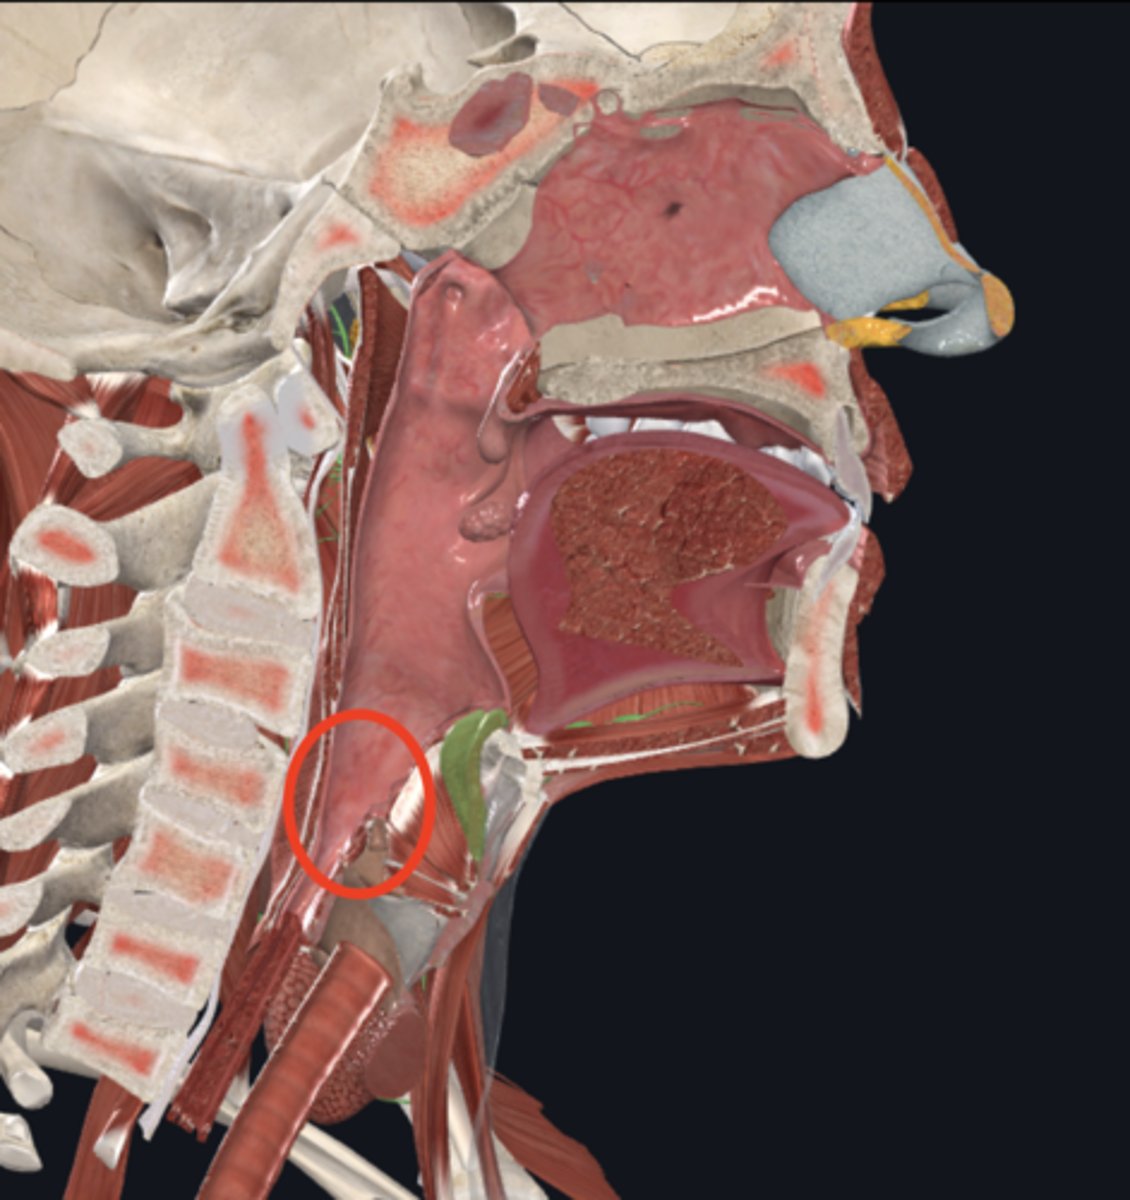

laryngopharynx

name the circled region

larynx

name the green portion

hyoid bone

name the green portion